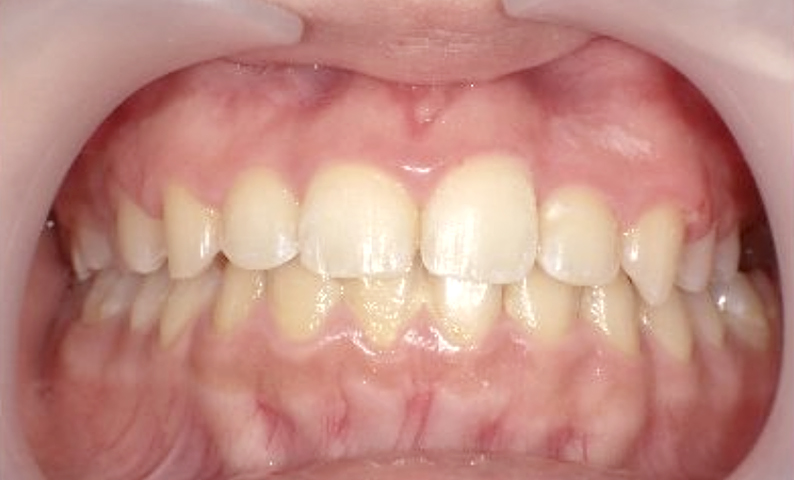

症例_002 上下顎の部分矯正

治療期間:7ヶ月金額:54万円+税女性前歯のガタガタ出っ歯八重歯

| Before | After |